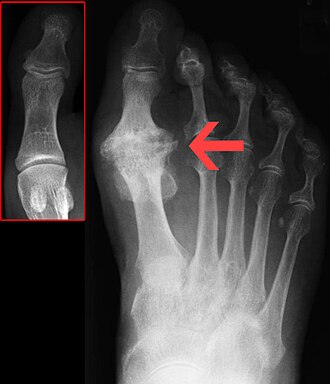

U težim slučajevima okolni su ligamenti i zglobna čahura deformirani koštanim proširenjima koji se javljaju u kasnijim fazama bolesti. U slučajevima artroze nisu prisutni crvenilo ili osjećaj topline u zahvaćenim zglobovima, međutim, mogu biti prisutni izljevi tekućine u zglobu i nateknuće. Česti fizički znakovi artroze su ograničena pokretljivost i atrofija mišića oko oboljelog zgloba. Heberdenovi čvorići, koji predstavljaju opipljive i vidljive osteofite kod artroze, mogu se uočiti na distalnim zglobovima prstiju ruku ili nogu, i izraženiji su kod žena, ali mogu biti prisutni i kod muškaraca. Upalne promjene obično su odsutne ili su vrlo malo izražene.